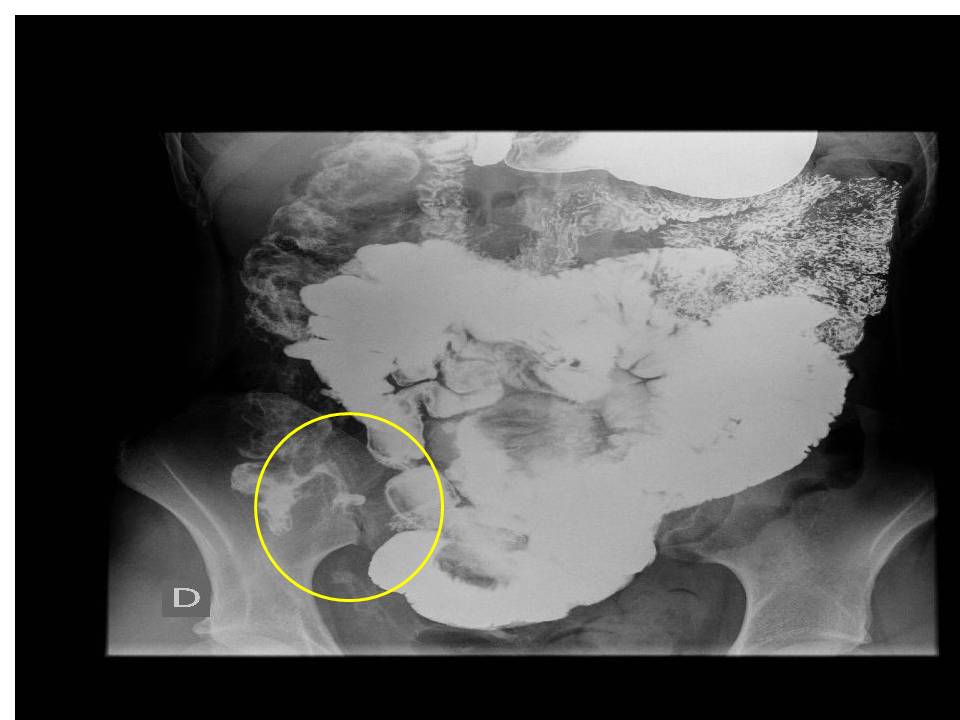

γ) Παλίνδρομη πλήρωση του τελικού ειλεού: Όταν υπάρχει υπόνοια παθήσεως του τελικού ειλεού μπορεί να γίνει βαριούχος υποκλυσμός και αφού γεμίσει το τυφλό, με εξάσκηση κατάλληλης πίεσης τοπικά το βάριο μπορεί να διέλθει μέσω της ειλεοτυφλικής βαλβίδας και να σκιαγραφήσει παλινδρόμως τον τελικό ειλεό.